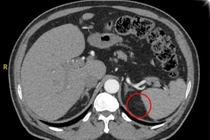

(khoahocdoisong.vn) - U tuyến thượng thận là bệnh dễ gây tai biến, dẫn đến tử vong. Bé 19 tháng tuổi không sốt, bụng to dần do mang trong mình khối u tuyến thượng thận kích thước lớn đẩy nhu mô gan và thận phải xuống dưới... đã được phẫu thuật thành công tại Bệnh viện Sản Nhi Quảng Ninh.